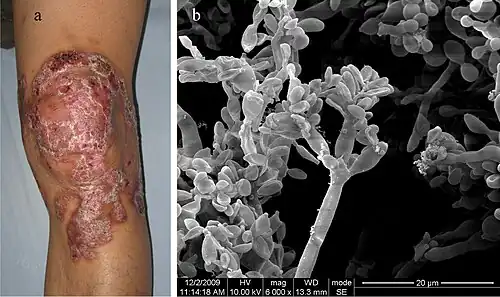

The initial trauma causing the infection is often forgotten or not noticed. The infection builds at the site over the years, and a small red papule (skin elevation) appears. The lesion is usually not painful, with few, if any, symptoms. Patients rarely seek medical care at this point.

Several complications may occur. Usually, the infection slowly spreads to the surrounding tissue while remaining localized to the area around the original wound. However, sometimes the fungi may spread through the blood vessels or lymph vessels, producing metastatic lesions at distant sites. Another possibility is secondary infection with bacteria. This may lead to lymph stasis (obstruction of the lymph vessels) and elephantiasis. The nodules may become ulcerated, or multiple nodules may grow and coalesce, affecting a large area of a limb.

Over months to years, an erythematous papule appears at the site of inoculation. Although the mycosis slowly spreads, it usually remains localized to the skin and subcutaneous tissue. Hematogenous and/or lymphatic spread may occur. Multiple nodules may appear on the same limb, sometimes coalescing into a large plaque. Secondary bacterial infection may occur, sometimes inducing lymphatic obstruction. The central portion of the lesion may heal, producing a scar, or it may ulcerate.

The prognosis for chromoblastomycosis is very good for small lesions. Severe cases are difficult to cure, although the prognosis is still good. The primary complications are ulceration, lymphedema, and secondary bacterial infection. A few cases of malignant transformation to squamous cell carcinoma have been reported. Chromoblastomycosis is very rarely fatal.

- ^ Ran Yuping (2016). "Observation of Fungi, Bacteria, and Parasites in Clinical Skin Samples Using Scanning Electron Microscopy". In Janecek, Milos; Kral, Robert (eds.). Modern Electron Microscopy in Physical and Life Sciences. InTech. doi:10.5772/61850. ISBN 978-953-51-2252-4. S2CID 53472683.